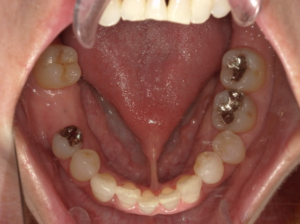

(治療前)

右下6番が欠損してることにより、噛み合わせの一部を失っていた状態です。

隣接歯があるため、ブリッジや義歯を補綴物として選択もできますが、隣接歯に負荷がかかってしまうため、予後を考えてインプラントを選択しました。